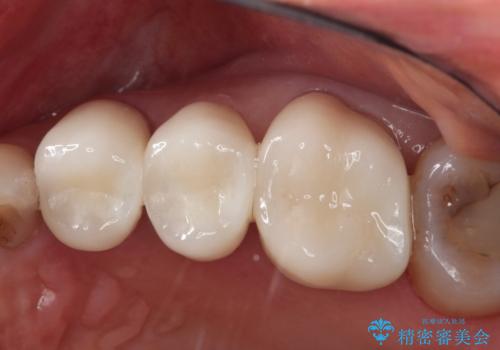

銀が目立つので白くしたい

担当医 青山卓弘